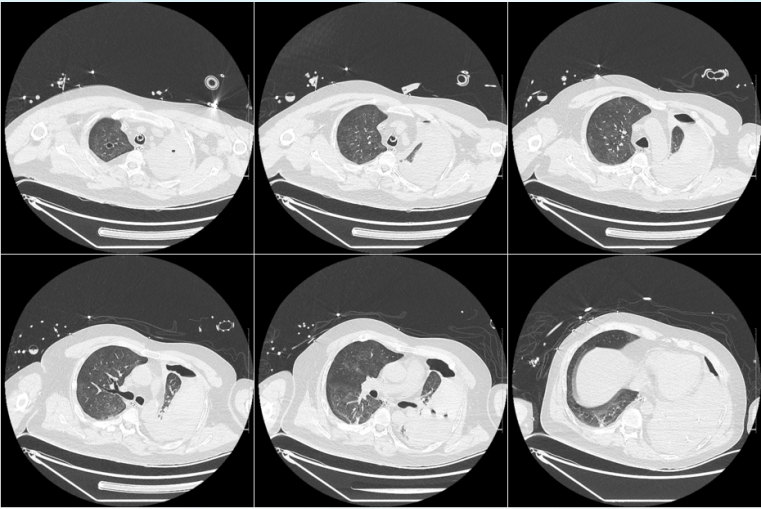

4. 影像学(外院,2025-04-26)

2025年4月26日患者外院胸部CT示:左侧胸腔积液伴左肺膨胀不全,左肺多发蜂窝状密度增高影,提示坏死性病灶可能,左肺上叶实性团块,占位性病变可能,右肺上叶小的厚壁空洞形成(图1)

1  患者外院胸部CT(2025-04-26)